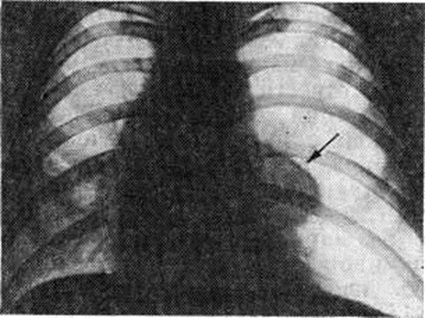

Для рентгенологического выявления пневмоторакса и его характера применяется многоосевое или полипозиционное исследование (смотри полный свод знаний). Рентгеноскопия грудной клетки в прямой проекции даёт ориентировочное представление о наличии Пневмоторакс и его характере и определяет выбор дополнительных методов исследования. Основным рентгенологическое признаком Пневмоторакс любой этиологии является участок просветления, лишённый лёгочного рисунка, расположенный по периферии лёгочного поля и отделённый от спавшегося лёгкого чёткой границей, соответствующей изображению висцеральной плевры (рисунок 1). При рентгенологическое исследовании выявляется связь плевральной полости с окружающей средой. Открытый травматический Пневмоторакс на вдохе характеризуется увеличением газового пузыря, дальнейшим спадением лёгкого, смещением органов средостения в здоровую сторону, смещением купола диафрагмы книзу. При закрытом травматическом Пневмоторакс рентгенологическое картина зависит главным образом от количества воздуха, скопившегося в плевральной полости, и связанного с этим внутриплеврального давления. Различают три типа закрытого Пневмоторакс: с давлением ниже атмосферного, выше и равным ему. При давлении ниже атмосферного количество воздуха в плевральной полости невелико. Лёгкое коллабировано незначительно, на вдохе оно увеличивается в объёме, на выдохе — спадается. При давлении выше атмосферного лёгкое резко коллабировано, его дыхательные экскурсии едва заметны, органы средостения смещены в здоровую сторону, диафрагма смещена книзу. Если давление при закрытом Пневмоторакс равно атмосферному, лёгкое коллабировано частично, дыхательные экскурсии сохранены, средостение смещено незначительно.

Рис. 1.

Рентгенограмма грудной клетки при правостороннем пневмотораксе: прозрачность правой половины грудной клетки повышена, стрелкой указано поджатое лёгкое, виден тонкий дренаж, введённый в правую плевральную полость для аспирации воздуха, слева — тень катетера в подключичной вене.